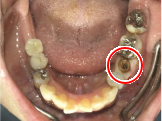

ブリッジの支台になっている奥の歯が、被せ物の中で虫歯になり、支台の役割を果たさず、前方の歯のみで支えられていました。前方の歯をそのままにして、後方の部分を切り離すと、そのまま取れてきました。中は、虫歯で歯根しか残っていない状況でした。この歯は、根管治療後、単独でオールセラミック冠を被せ、歯のないところにインプラントを埋入しました。

冠の中で大きな虫歯になり支台の役割を果たしていませんでした。

【インプラント埋入前】

冠はブリッジを切断しただけで取れてきました。軟化象牙質を取り除いたところ、歯根しか残っていない状況で保存できるかどうかのぎりぎりのところでした。